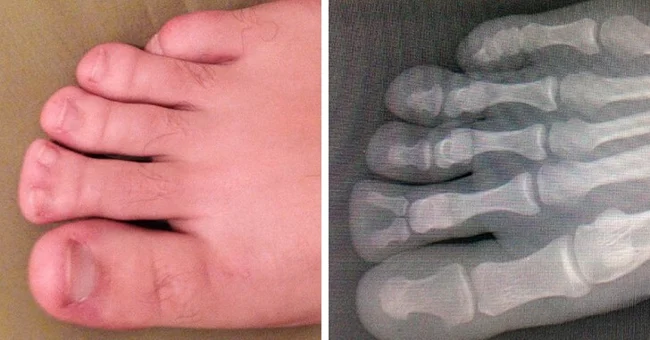

Раздвоенный палец